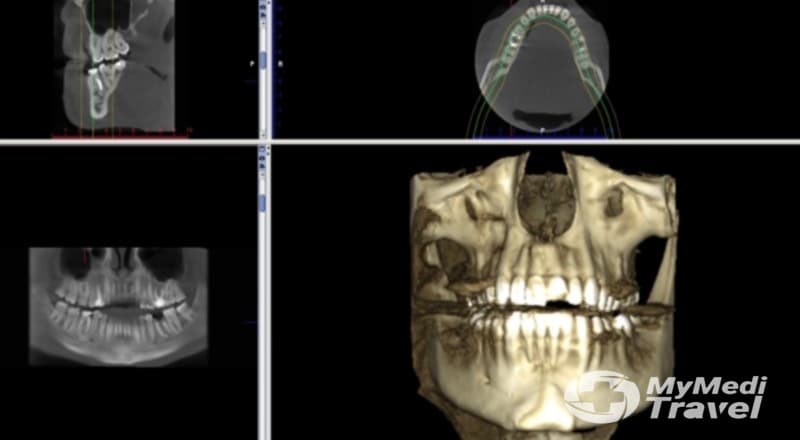

Dental X-Rays

Prices Start From $1

See prices & compare results